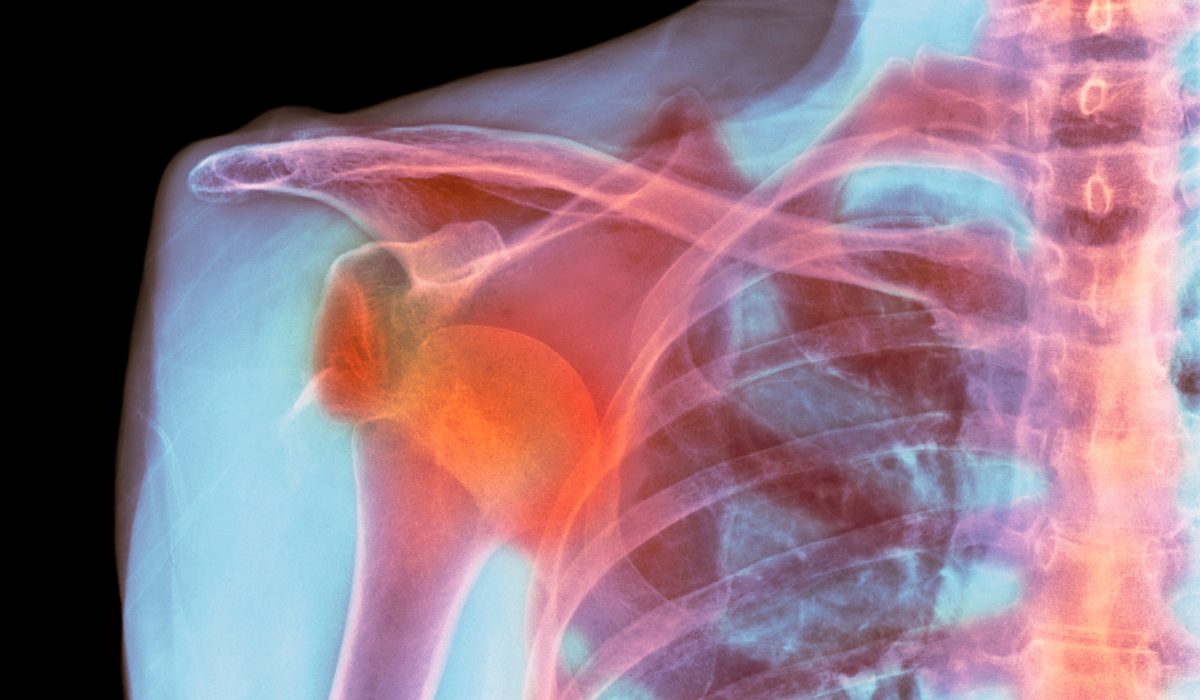

Shoulder joint replacement, also known as shoulder arthroplasty, is a surgical procedure in which damaged parts of the shoulder joint are replaced with artificial components to restore function and relieve pain. It is primarily recommended for patients suffering from severe shoulder arthritis, complex fractures, or long-standing rotator cuff injuries that have led to joint deterioration. The procedure can be total (replacing both the ball and socket), partial (replacing only the humeral head), or reverse (used when rotator cuff muscles are non-functional).

The goal of this surgery is to reduce chronic pain, improve range of motion, and allow patients to return to their daily activities with greater ease. Over time, conditions like osteoarthritis, rheumatoid arthritis, or post-traumatic arthritis can cause the cartilage in the shoulder to wear away, leading to stiffness, grinding, and pain. When medications, injections, and physiotherapy no longer help, joint replacement becomes a reliable and lasting solution.